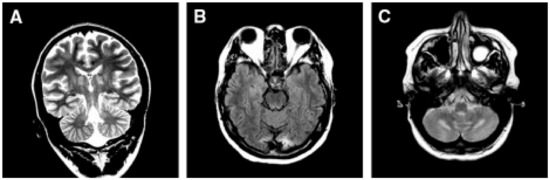

Clinical Definition

- Barkovich, A.J.; Good, W.V.; Koch, T.K.; Berg, B.O. Mitochondrial Disorders: Analysis of Their Clinical and Imaging Characteristics. AJNR Am. J. Neuroradiol. 1993, 14, 1119–1137. [Google Scholar] [PubMed]